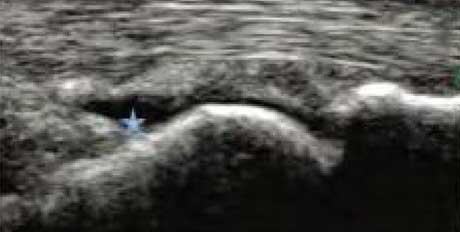

2、清晰显示滑膜异常形态,定量评估RA炎性

类风湿性关节炎以滑膜炎为基本病理改变,超声可观测到关节暗区的范围及厚度,判断有无滑膜增厚、显示不同程度的滑膜均匀或不均匀增厚,分辨滑膜呈绒毛状、团状或结节状结构向关节腔突起的形态。通过对滑膜厚度、水肿、炎性细胞浸润状况的分级、定量评估RA关节内滑膜的炎性程度。

Ⅰ级滑膜增生

轻度滑膜增生,不超过骨面点连线

Ⅱ级滑膜增生

滑膜增生超过骨面点连线,呈绒毛状,但不越过骨干

Ⅲ级滑膜增生

滑膜增生超过骨面点连线,呈团块状延伸超过一侧骨干